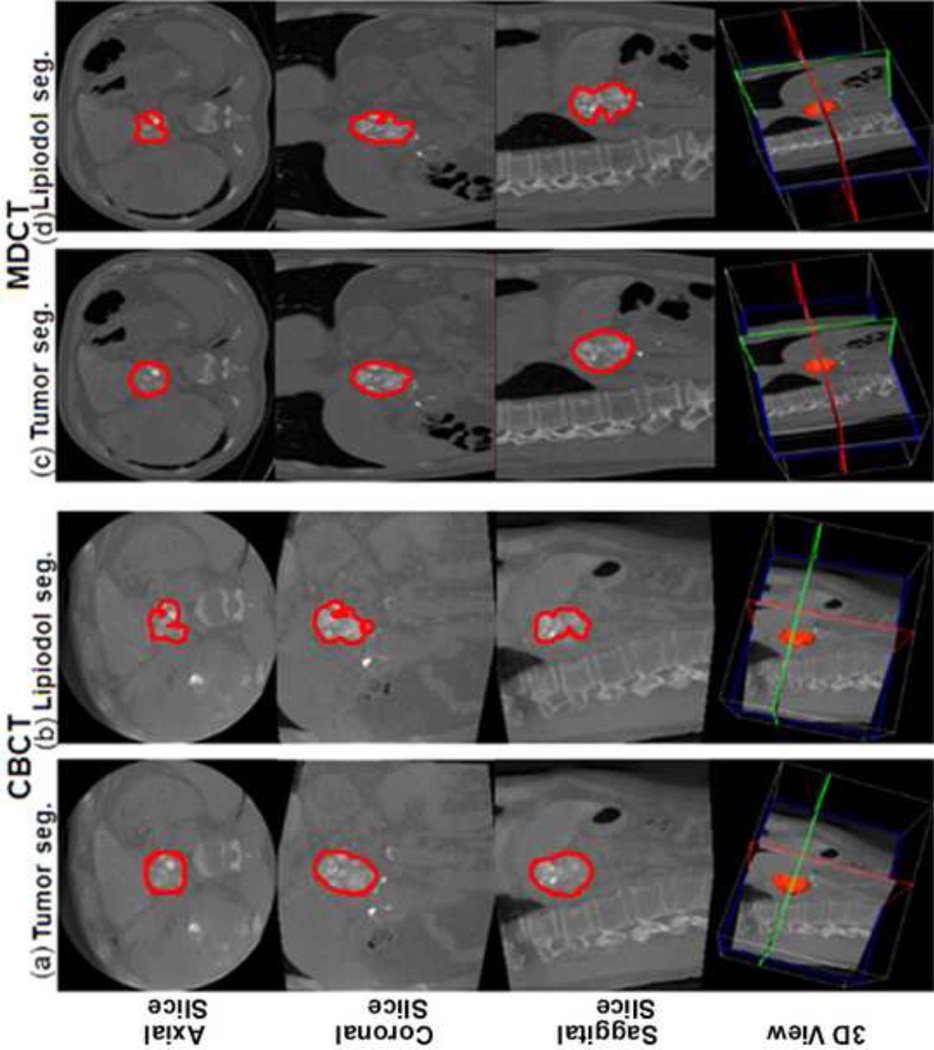

The volumes of the entire tumor and only the lipiodol retention on CBCT and MDCT were measured using the 3D segmentation software (Fig 2, Fig 3). As shown in Table 2, the average volume of the whole tumor and the lipiodol retention, and the calculated average percentage of lipiodol retention in the target tumors on CBCT were not significantly different when compared to MDCT. Additionally, the high correlation in both the tumor volume and the lipiodol volume between CBCT and MDCT imaging was evidenced by the linear regression analysis shown in Figure 2. The R2 value for the tumor volume and the lipiodol volume were 0.919 and 0.903 respectively (Fig 4), indicating the strong agreement between CBCT and MDCT.

Figure 2.

Tumor and lipiodol segmentation on CBCT and MDCT images (the same case as in Figure 1). The top row shows axial slices, the second row coronal slices, the third row sagittal slices and the bottom row the three-dimensional (3D) projected volume. (a) The tumor segmentation on CBCT images. Tumor volume= 44.5cm3. (b) The lipiodol segmentation on CBCT images. Lipiodol volume=31.9cm3. The calculated percent of lipiodol retention on CBCT=71.7%. (c) The tumor segmentation on MDCT images. Tumor volume=42.1cm3. (d) The lipiodol segmentation on MDCT images. Lipiodol volume=27.2cm3. The percent of lipiodol retention on MDCT=64.6%. Note the special care to avoid areas with pronounced necrosis and non-lipiodol deposition during lipiodol segmentation. Seg=segmentation.